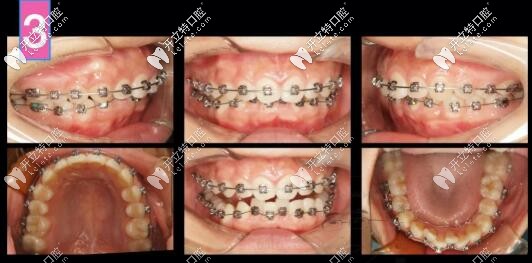

骨性二類凸嘴正畸內收3-4mm側貌效果,金屬自鎖(拔牙+骨釘)

骨性齙牙不手術,單純正畸內收3-4mm側貌效果變化明顯嗎?不如來看一例金屬自鎖(拔牙+骨釘)矯正案例。

26歲女孩,來診主訴:嘴凸,大笑露牙齦,強烈訴求是解決嘴凸問題。

側貌微凸,深覆合

右側磨牙尖牙關系II類,左側I類,

深覆合覆蓋5mm,下頜牙弓擁擠度5mm

計劃支抗釘整體推上頜牙列向后、壓低上牙來解決深覆合和微凸問題,選用了標準轉矩DamonQ托槽。

凸嘴自鎖托槽矯正案例

第6個月,上下都排齊了,下頜還是沒有主動跑出來,此時詞用支抗釘整體上牙內收再看看

凸嘴支抗釘內收

到了第八個月,嘴更凸了,因為上前牙恢復直立于牙槽骨中,凸度增加,臉頰還凹了,

因為下前牙唇傾出去,磨牙伸長,深覆合解決,下頜平面角加大

齙牙深復合牙齒矯正案例

前牙區(qū)支抗釘安排上!

矯正到34個月,姑娘終于露出久違的燦爛!

骨性二類齙牙單純正畸側貌效果圖

骨性二類凸嘴單純正畸牙齒內收3-4mm側貌效果圖

上前牙大量的壓低和內收,深復合改善。